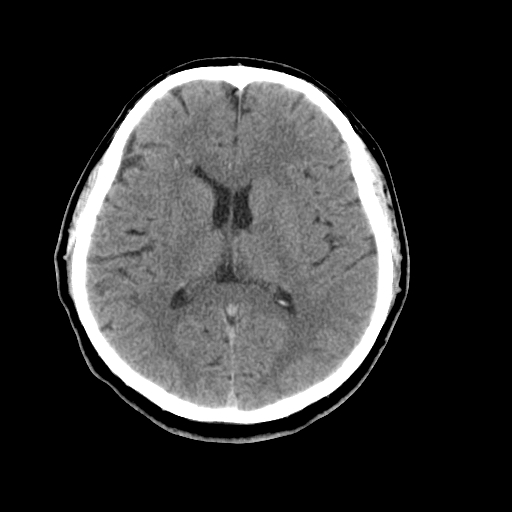

以下是引用liuyue在2008-4-28 13:34:00的发言:[br]右额叶条状高密度影,边缘清楚,周围未见水肿及占位.[br]考虑:血管畸形可能性大.[br]建议:强化ct扫描或mri检查.除外脑回钙化.

以下是引用论黑辩白在2008-4-28 12:53:00的发言:[br]右额叶局限性脑萎缩,右额叶见条状高密度影,建议mri进一步检查。[br][br][本贴已被 论黑辩白 于 2008-4-28 13:08:16 修改过]